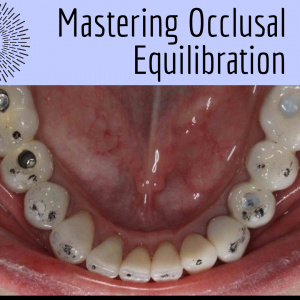

Mastering Occlusal EquilibrationGordon J. Christensen, DDS, MSD, PhD & Valinda Johnston, BS, CDA We are seeing unprecedented levels of cracked natural teeth, TMD, and tooth loss because of occlusal malfunction. Rigid, wear-resi...... |